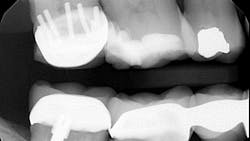

P.S. I counted seven pins.